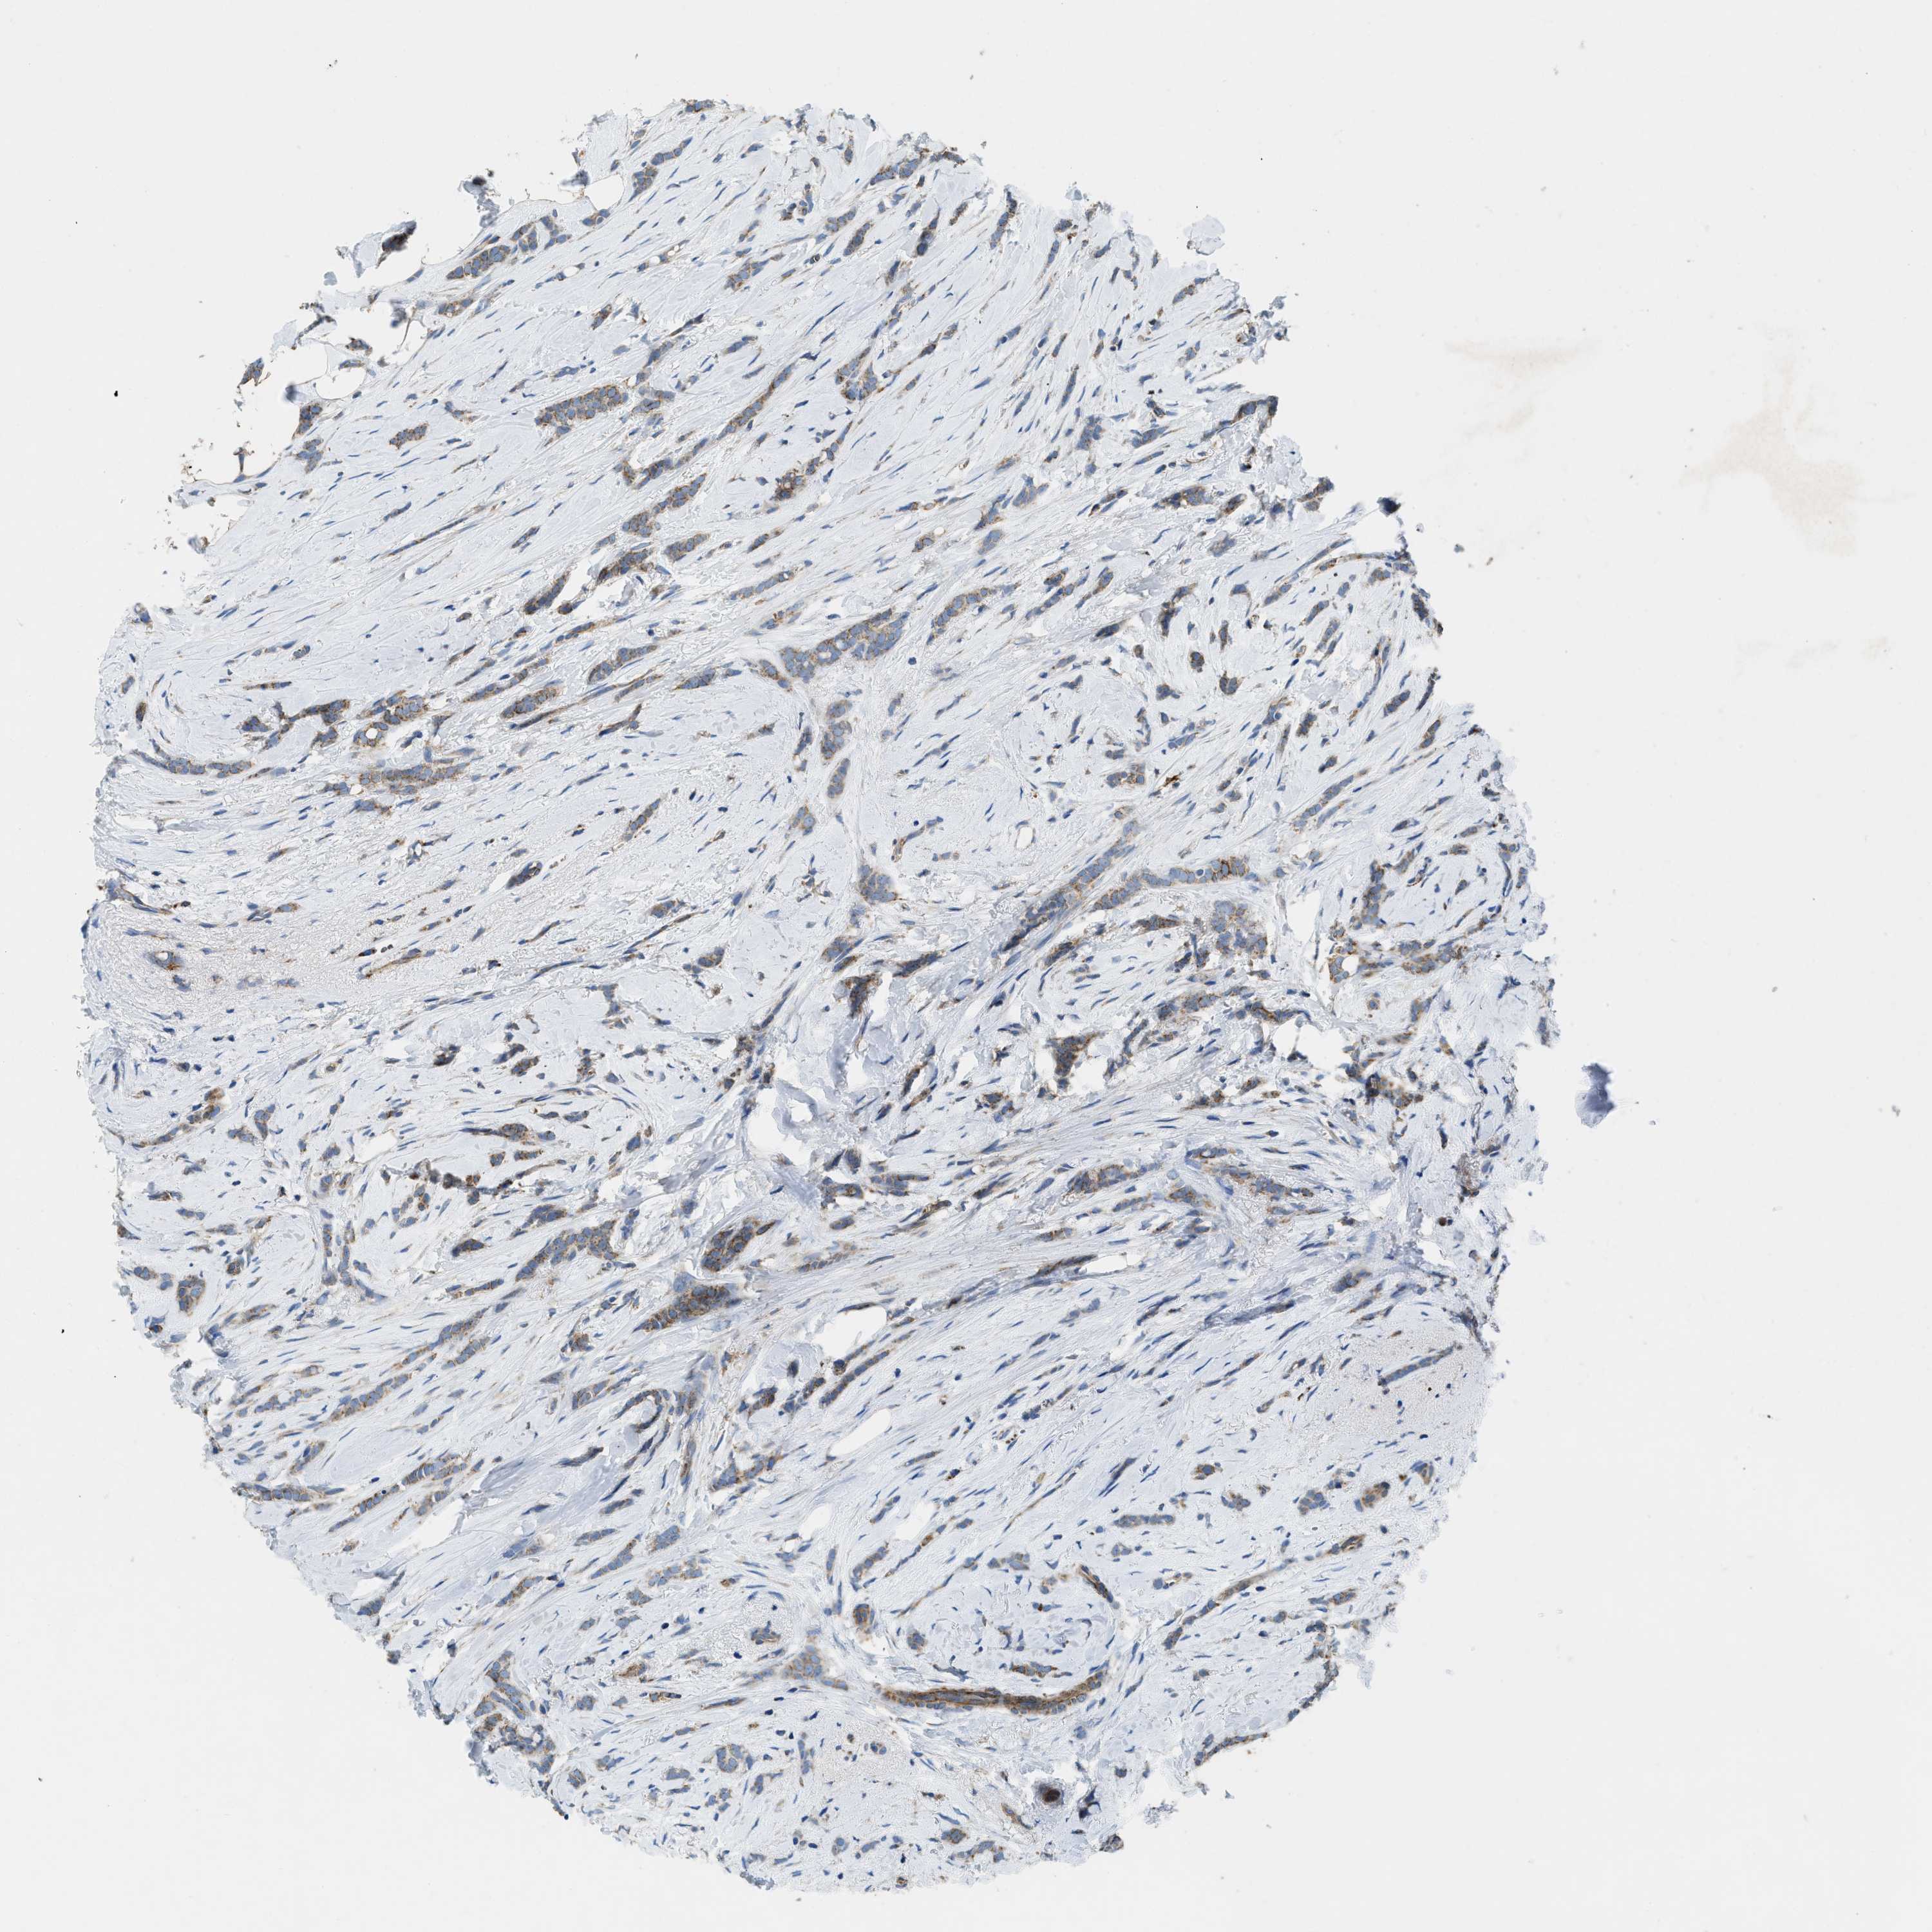

BRCA TCGA BRCA VALIDATION PROTEIN EXPRESSION